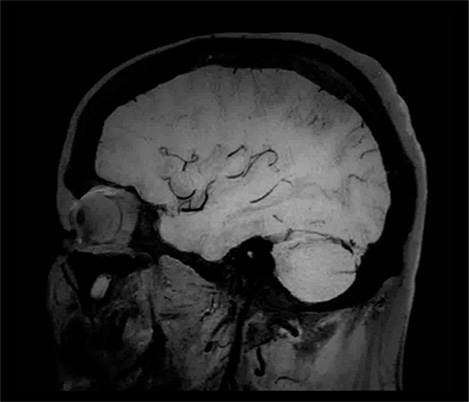

De la colaboración El Dr. Tetsuya Yoneda, Universidad de Kumamoto, Japón, habla sobre su colaboración con Philips en una técnica llamada SWIp desarrollada para la imagenología ponderada por susceptibilidad.

...a la práctica clínica El Dr. Chip Truwit, Centro Médico del Condado de Hennepin, Minneapolis, EE. UU. explica cómo SWIp se convirtió en una parte integral de todas las exploraciones de traumatismo por resonancia magnética.